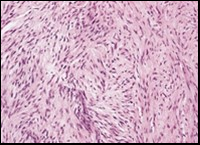

Figure 2.Low grade fibromyxoid sarcoma exemplifying intermingled foci of fibrous and myxoid regions of spindle-shaped cells with minimal pleomorphism and absence of mitosis (10).

Macroscopically,the neoplasm is gradually progressive, painless, firm, tan coloured, well circumscribed, grossly infiltrative, soft tissue mass of magnitude varying from one centimetre to 18 centimetres, commonly of 6 centimetres diameter. Cut surface is fibrotic with focal myxoid areas4. On fine needle aspiration cytology, the cellular neoplasm is configured by spindle-shaped cells. Tumour cells contain scant, wispy cytoplasm, uniform, elongated nuclei and miniature, inconspicuous nucleoli. The background is prominently myxoid. Significant nuclear pleomorphism or mitotic activity is absent. However, cogent diagnosis on cytology may be challenging 4.5. On low power, the well demarcated neoplasm is composed of alternating foci of myxoid and fibrous tissue. Giant rosettes are intermingled with zones of whorled cellular aggregates recapitulating preliminary rosettes.

Bland tumour cells depict monotonous, hyperchromatic nuclei. Tumour areas can exhibit prominent curvilinear, arching or plexiform vasculature. Mitotic activity is exceptional 4, 5.

Typically, low grade fibromyxoid sarcoma is comprised of a whorled cellular pattern with intermingled fibrous and myxoid areas. Also, minimally cellular areas of collagenous tissue are denominated, composed of uniform spindle-shaped cells4, 5. Unique morphologic pattern of hyalinising spindle cell tumour configuring giant rosettes can appear in certain low grade fibromyxoid sarcomas4, 5.

The minimally to moderately cellular neoplasm is composed of bland, fusiform or spindle-shaped cells with scarce cytoplasm and angulated nuclei. Also, whorled cellular aggregates are exhibited. Focal to diffuse cellular whorls are intermingled within a dense, collagen-rich stroma. Abrupt, focal transition to myxoid areas can be discerned. Roughly 45% neoplasms depict foci of epithelioid cells. Nearly 40% tumours display enlarged, inadequately configured collagen rosettes2, 4.